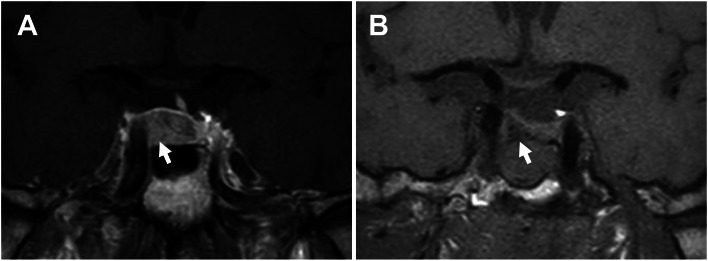

Fig. 1.

Pre- and postoperative findings of pituitary magnetic resonance imaging (MRI). A A preoperative T1-weighted image with contrast enhance. This image shows a 12 mm pituitary tumor as a less enhancing lesion (white arrow). The normal pituitary gland is shoved to the upper left of the sella turcica. B A postoperative T1-weighted image without contrast. After tumor resection (white arrow), the normal pituitary gland is decompressed

The pituitary tumor was completely removed by transsphenoidal surgery, confirmed by magnetic resonance imaging (Fig. 1B). Based on histopathological analysis, the tumor was diagnosed with a GH-producing adenoma (Fig. 4).